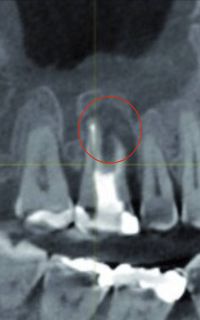

Bakterien toter, abgestorbener Zähne, welche eine Entzündung an der Wurzelspitze zeigen, produzieren Toxine, sog. Schwefelwasserstoffverbindungen, welche zu einer irreversiblen Hemmung am aktiven Zentrum vieler lebenswichtiger körpereigener Enzyme führen und somit vielfältige System- und Organ-Erkrankungen hervorrufen können.